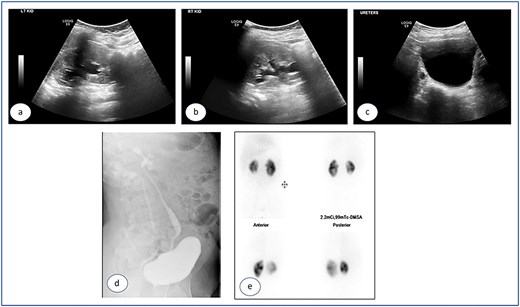

Urgent cystoscopy was performed, and bilateral double-J stents were placed. Both orifices were observed, accompanied by substantial inflammatory masses surrounding them, disproportionate to the initially injected mounds; yet, they did not obstruct the smooth passage of the stents. The patient recovered satisfactorily and was discharged with normal diuresis. One month later, the right double-J stent was extracted, demonstrating a substantial reduction of the inflammatory masses at the uretero-vesical junction. Two months post injection the left stent was removed and, at that point, no inflammatory masses were present. The mucosa appeared normal, exhibiting significant bulges at the Deflux injection sites. Subsequent ultrasound examinations revealed the absence of hydronephrosis bilaterally (Fig. 3a–c), accompanied by normal levels of creatinine and urea. The prophylactic antibiotics were discontinued and the patient was monitored for 5 years, remaining asymptomatic with no more urinary tract infections.

Ultrasound images taken 1 month after the removal of both double J stents, showing no hydronephrosis in either kidney—the left (a) and right (b)—and urinary bladder with Deflux in place (c).